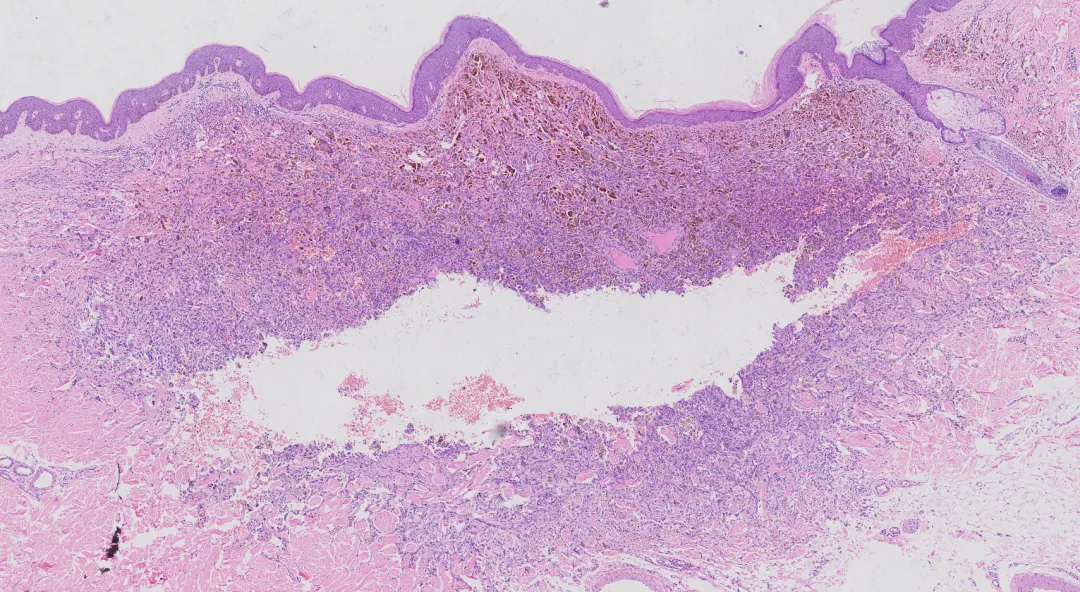

角化过度,表皮增生肥厚,皮突延长,肿瘤位于真皮内,排列较紊乱,肿瘤中央可见出血性裂隙,真皮乳头部可见无浸润带。

•大体:边界较清,切面灰褐,实性为主伴出血性囊腔,似动脉瘤。

•镜下(四联征):

b.假血管瘤样腔隙:腔隙充满血液,无内皮衬覆(关键)。

d.包膜外淋巴浆细胞套:可见生发中心。